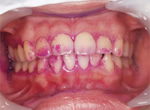

PMTC直後のお口の中の写真です。

染出しして赤くなった部分の汚れを取り除き、舌で歯を触るとツルツルとした感触になります。歯茎の色がきれいなピンク色になって引き締まっています。